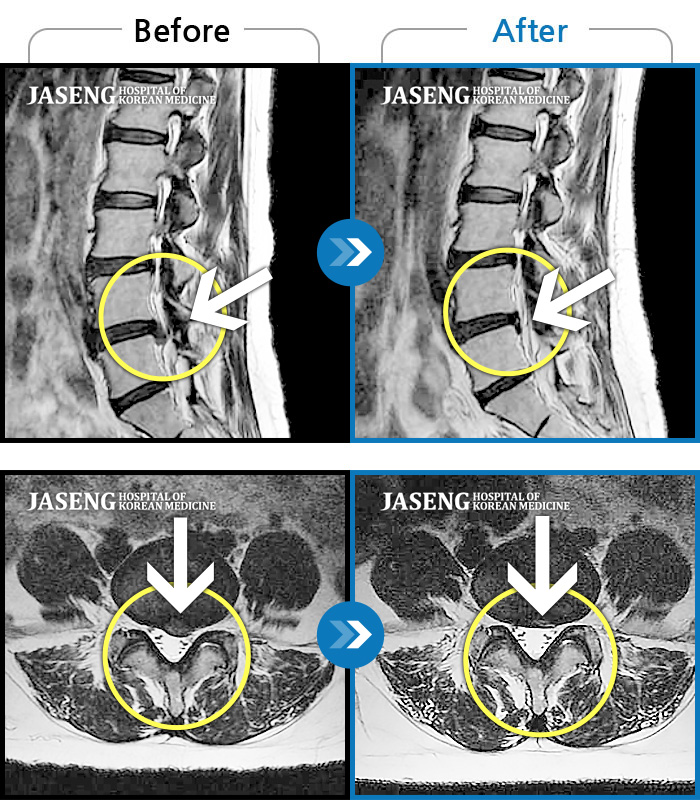

허리디스크

수원 · 김태성 원장

우측 허리 통증과 우측 다리 방사통으로 활동하기 힘든 상태

촬영시기

2021.02.03 ~ 2021.07.09

2022.03.25